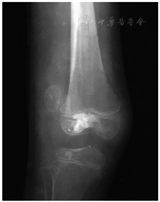

一期切断髂胫束中挛缩的条索,行胫骨干骨牵引。6周后二期手术,去除骨牵引,行髂胫束和股二头肌肌腱"Z"形延长;在肌间隔剥离股外侧肌,骨膜下推开股四头肌,髌骨处切断股外侧肌腱膜并上移固定在股四头肌腱外侧,切开髌外侧支持带,松解髌骨,完成外侧软组织松解。在髌骨内缘切断股内侧肌腱膜,外移固定在股四头肌腱前侧;重叠缝合髌内侧支持带;鹅足前移,固定在髌腱内侧,强化内侧软组织稳定。胫骨内侧平台隆凸阻碍胫骨完全复位(图3),因此在胫骨内侧平台前缘切开小口,刮除少量骨质,按压平台隆凸,使之与股骨内髁匹配。术中未发现异位钙化组织。术后用斯氏针经髁间交叉固定膝关节于屈曲20°位,长腿石膏托固定。5周后拔除斯氏针并开始进行膝关节屈伸活动锻炼,6周后扶双拐轻负重行走。

Freyschmidt[3]报告了23例蜡泪样骨病,仅5例有典型的蜡泪样表现。他认为蜡泪样骨病X线片表现的多样性已超出其典型特征,并根据X线表现提出五种类型:类骨瘤型、经典蜡泪型、类条纹状骨病型、类骨化性肌炎型和混合型。类条纹状骨病型很容易与条纹状骨病混淆,鉴别要点是前者条纹较宽,偏居一侧,骨皮质增厚;后者条纹较细,自干骺端向骨干延伸,均匀分布在髓腔内,双侧发病,骨皮质正常[3,8]。本例股骨髓内条纹骨较宽,偏居外侧,同侧皮质骨增厚,骨骺内有致密的骨癍,应诊断为蜡泪样骨病类条纹状骨病型。